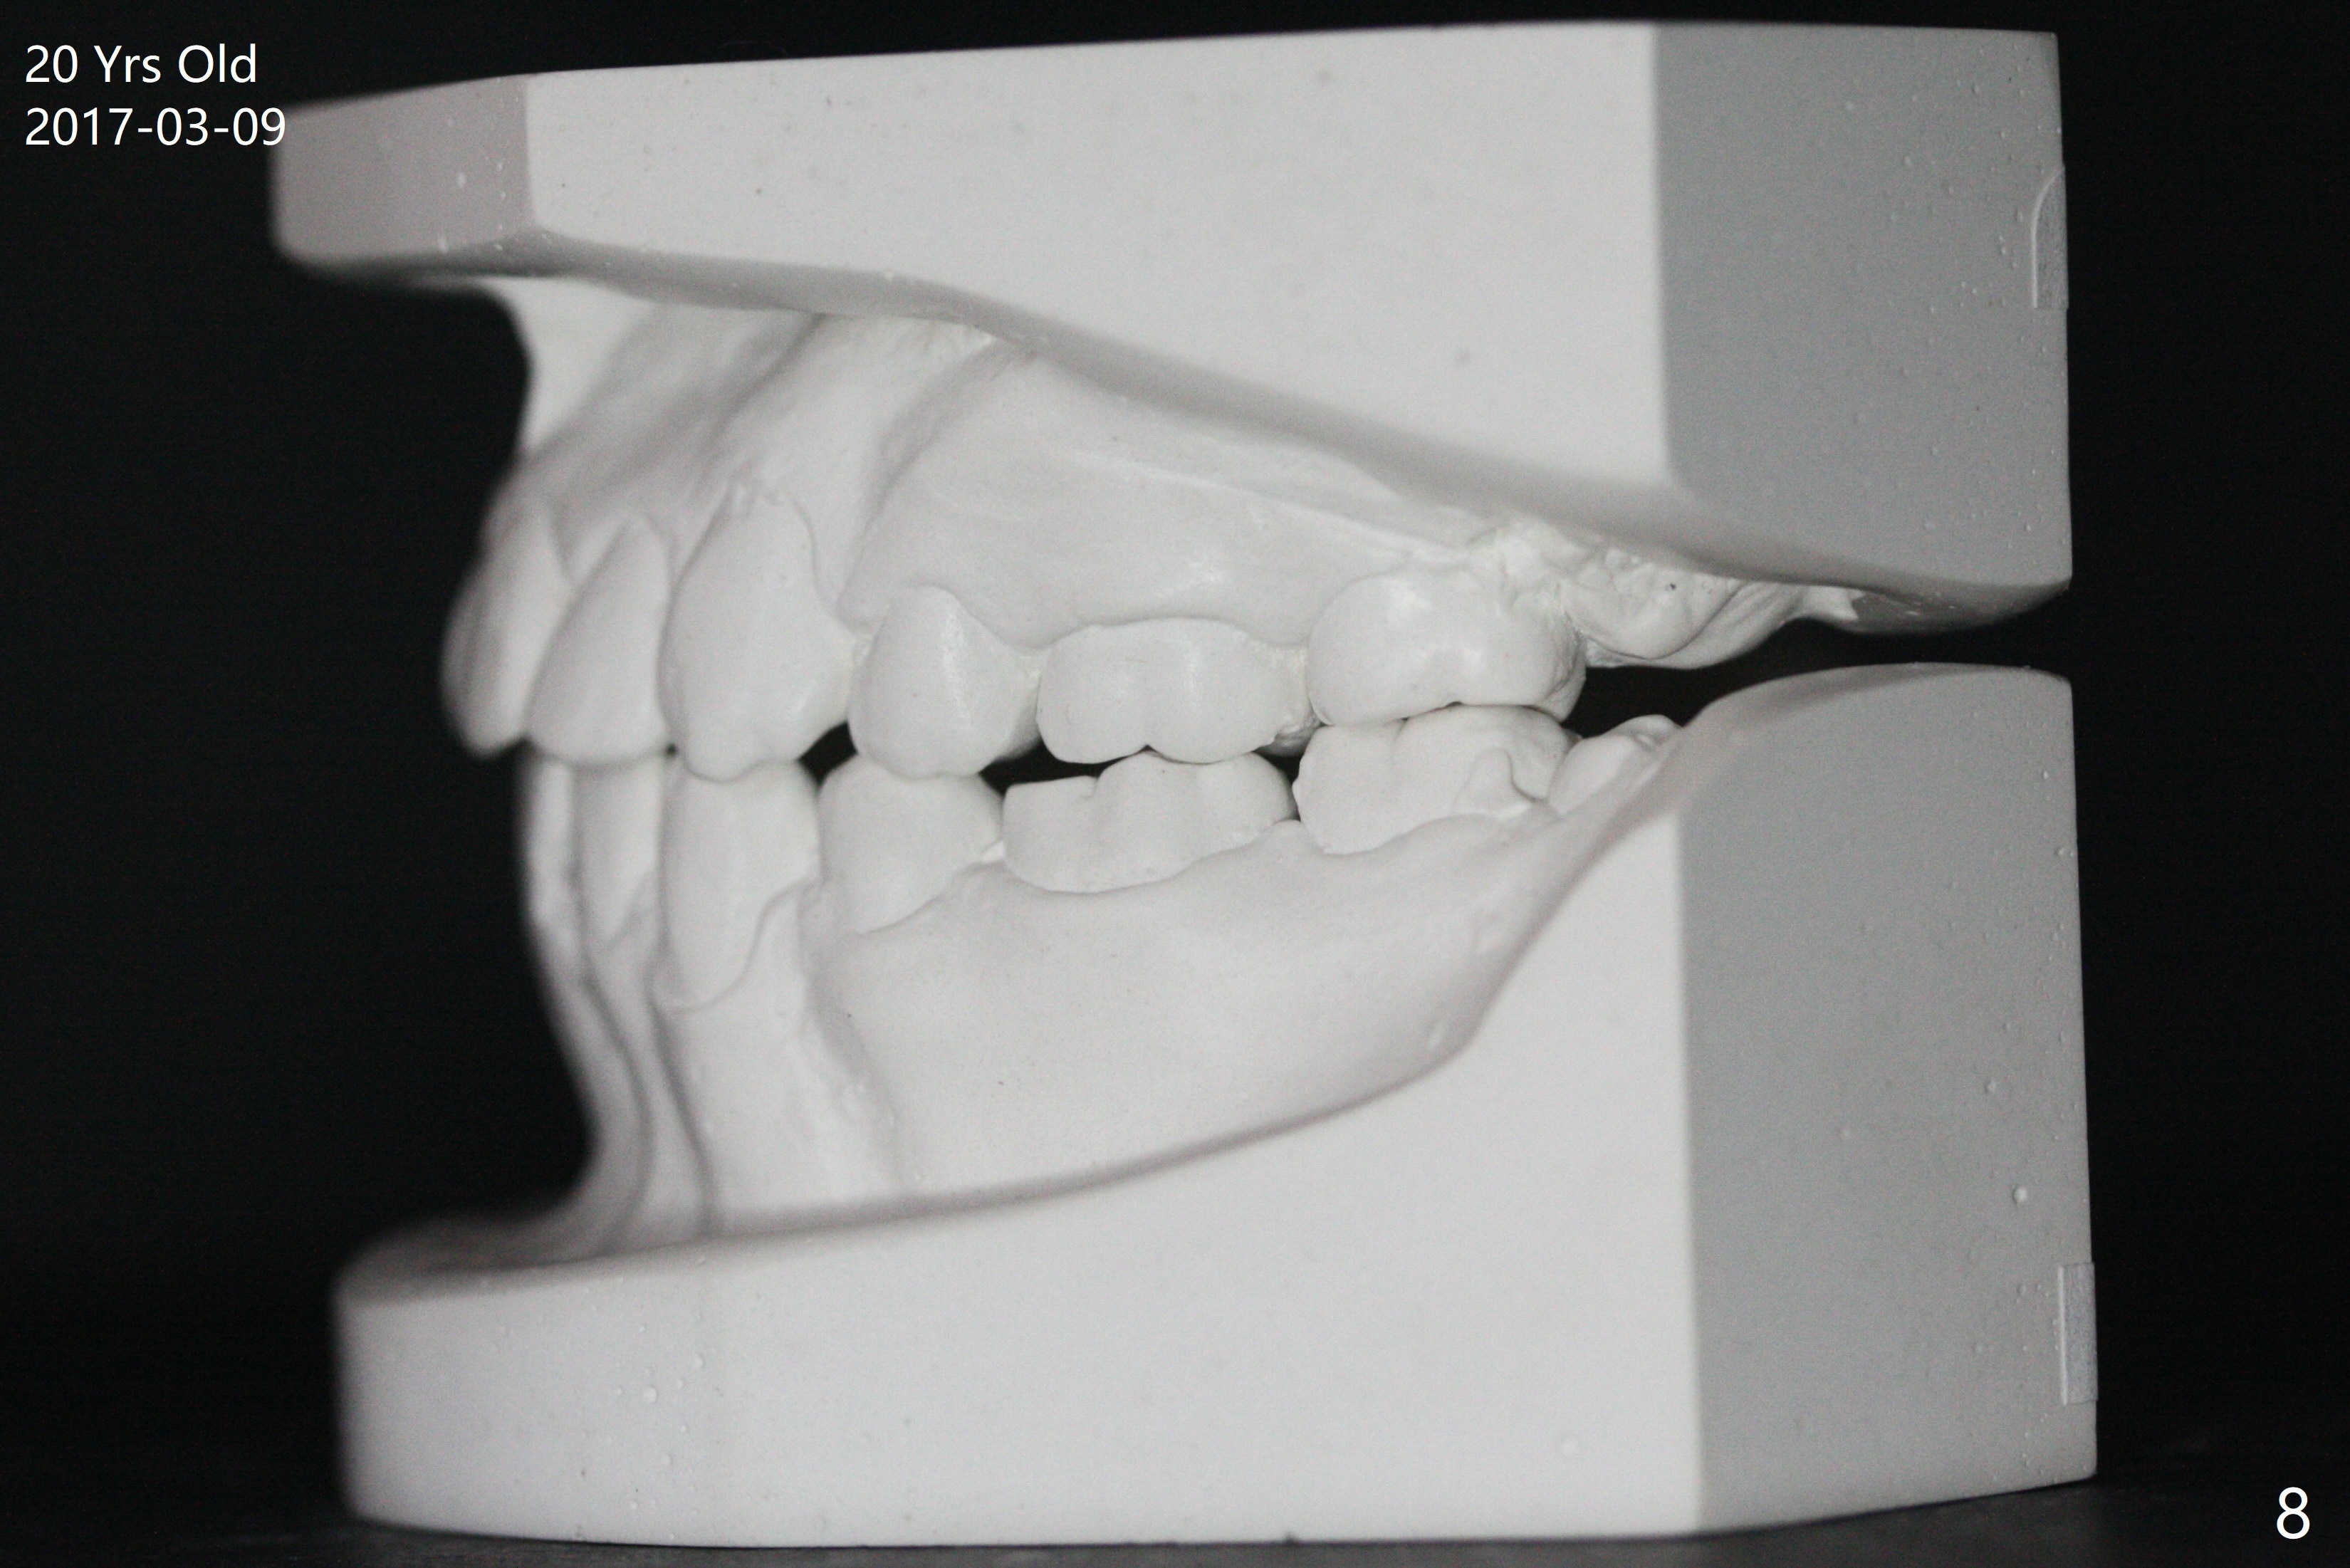

A 16-year-old man has severe crowding, but the open bite is ignored (Fig.1,4,7,10,13). The orthodontic treatment lasts 4 years 5 months, including failure to return for a period of time. The open bite seems to have been corrected (Fig.2, 5, 8, 11, 14). Suction down retainers are provided. In less than 2 years, the patient returns requesting remaking retainers. It appears that open bite relapses (Fig.3,6,9,12,15), as related to supraeruption of the lower 2nd molars (Fig.6,9 arrows). The latter is apparently associated with the erupting 3rd molars.